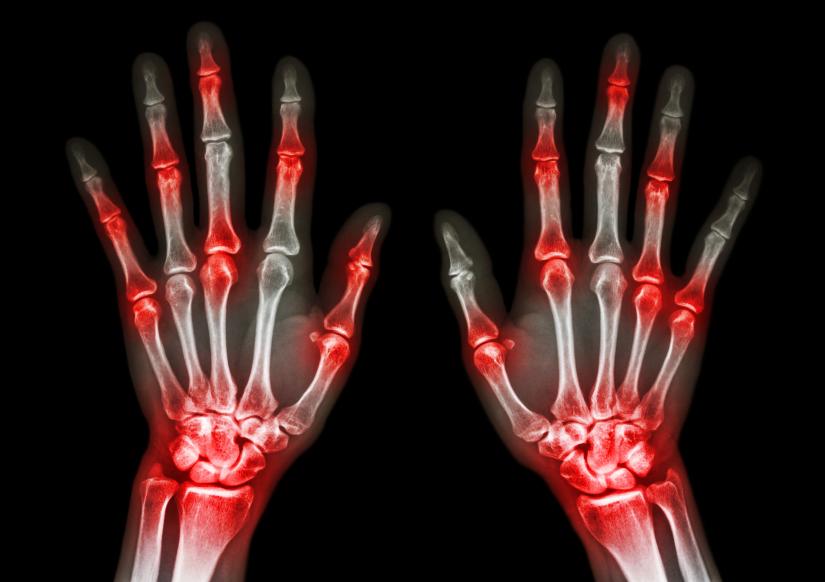

En primer lugar, es necesario destacar que se trata de dos enfermedades distintas y la lesión se produce en distintos puntos de la articulación:

• La artritis es una enfermedad que se produce al inflamarse la membrana sinovial de las articulaciones, aquella que alimenta, protege y recubre los cartílagos.

• La artrosis también es degenerativa pero aparece a causa del desgaste del cartílago, que es el tejido elástico que recubre los extremos de los huesos y ambos forman las articulaciones.

• La artritis reumatoide tiende a afectar a las muñecas, nudillos y dedos, pies, codos, hombros, caderas, así como a rodillas o tobillos.

El dolor de una y otra enfermedad articular también es distinto, y aunque el dolor producido por la artrosis —de tipo mecánico— puede mejorarse y tratar con medicación y reposo, el dolor causado por la artritis no mejora con el reposo sino que puede llegar a empeorar, por ejemplo por la noche.